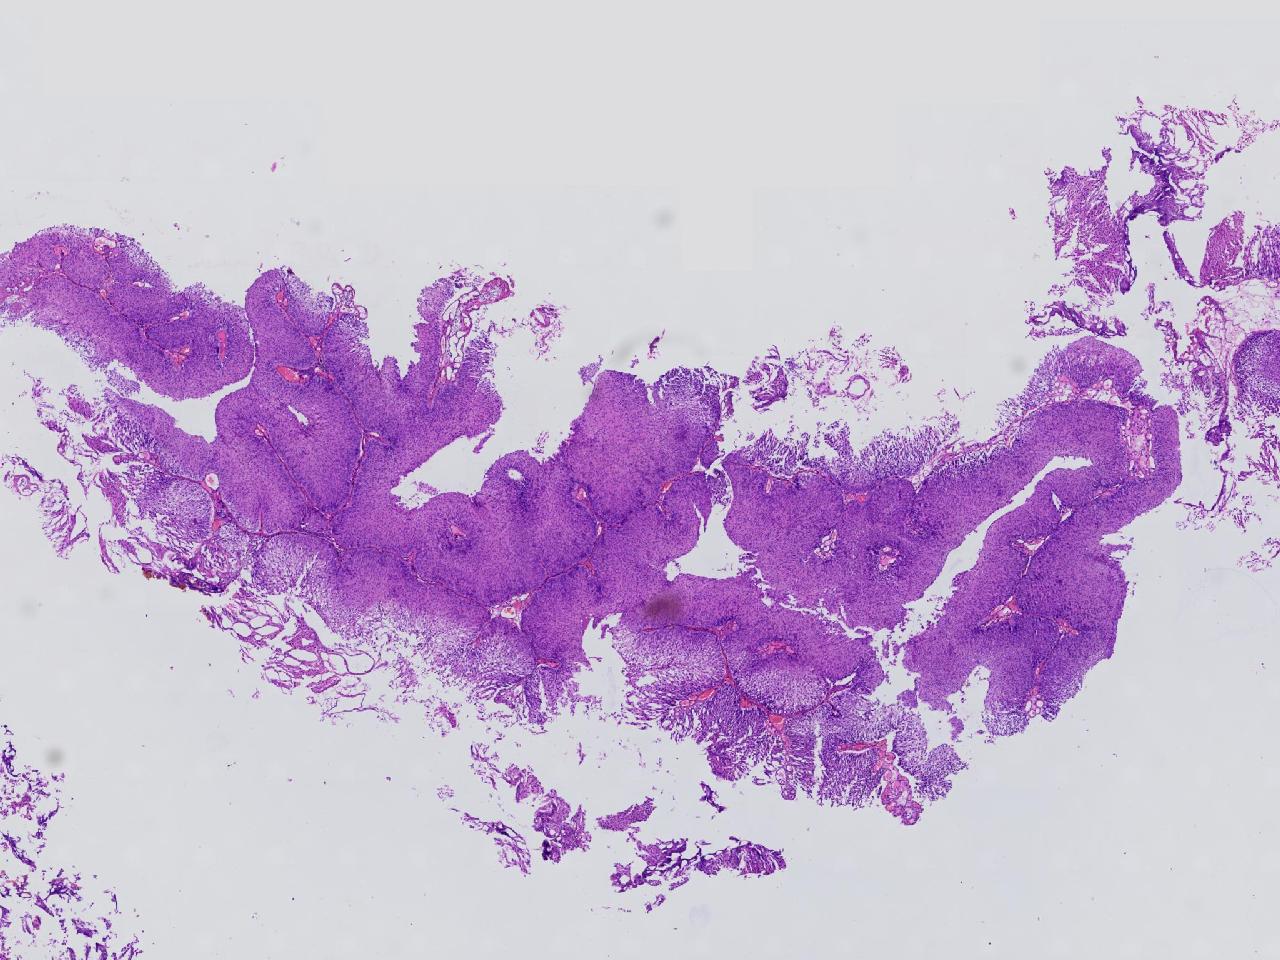

男,79岁,膀胱肿物。

膀胱肿物

灰白色不整形软组织多块,2X1X1厘米。

考虑:乳头状尿路上皮癌

乳头状尿路上皮癌,低级别。

这几张图片上没有看到明确的浸润。